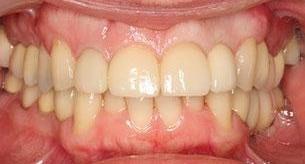

This young dad had four congenitally missing upper teeth. He had a quick orthodontic treatment and a large span bridge placed in as a teenager. He never smiles with teeth showing.

After many years of wear and tear, some of the work started to break and fail. We removed the defective bridges, managed to save all the existing teeth and placed four implant supported crowns in. The patient is very happy to be able to smile confidently now.